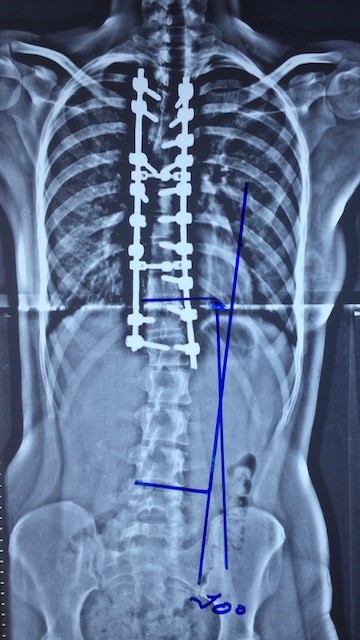

Radiografia da coluna pois correção da escoliose torácica e com correção

Compensatória da escoliose lombar